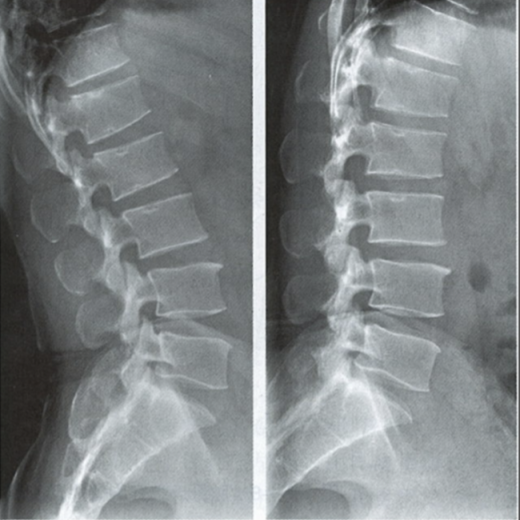

腰椎動力位,也稱為過屈過伸位,可以理解為兩個極限體位下的側(cè)位片,腰椎動力位通過做最大程度彎腰(過屈)和后仰(過伸)的動作拍攝側(cè)位片,來觀察腰椎在極限活動下的表現(xiàn)。如果說腰椎側(cè)位片能靜態(tài)體現(xiàn)椎體的解剖學(xué)結(jié)構(gòu)、序列及生理曲度改變,那么腰椎動力位則是評估腰椎動態(tài)功能性的檢查。

腰椎過伸位:是指腰部盡可能向后伸展,以雙髖關(guān)節(jié)位支撐點,運動前后骨盆位置無改變。腰椎過伸時,向前的曲度大于生理曲度,上部向后傾斜。

腰椎過屈位:是指腰部盡可能向前彎曲,以雙側(cè)髖關(guān)節(jié)位支撐點,運動前后骨盆位置無改變。腰椎過屈的表現(xiàn)位向前的曲度減小、變直,上部向前傾斜。

當(dāng)1度及以上的滑脫時才可以在普通腰椎側(cè)位上觀察到,而1度以下的滑脫或失穩(wěn)則在普通側(cè)位片上難以發(fā)現(xiàn),這時候就需要借助腰椎動力位進(jìn)行診斷。

腰椎動力位 左圖為過伸位、右圖為過屈位